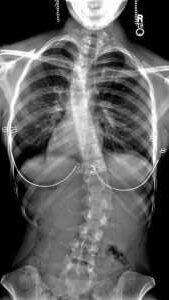

A scoliosis is a curvature of the spine, while a laterally tilted pelvis is a misalignment of the pelvis. However, the two conditions are closely linked. A tilted pelvis can contribute to scoliosis, and scoliosis often creates or worsens pelvic tilt. They are separate condition, but can be closely interconnected.

X-ray image of someone with scoliosis